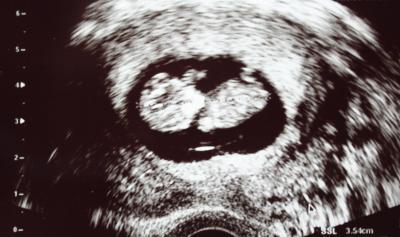

Hallo ihr Lieben, leider komme ich meistens nur am WE dazu, hier auch mal mitzuschreiben, unter der Woche bin ich viel unterwegs und schaffe es abends höchstens, mal quer durch eure Beiträge zu lesen. Am Freitag habe ich ENDLICH den Mutterpass bekommen HB-Wert ist prima, alle anderen Werte sind auch gut. Beim US vor 2 Wochen wurde ich ca. 5 Tage zurückgestuft, nun sind es nur noch 2 und der ET vom 20.8. stimmt (da der ES aber sehr spät war, gehe ich eher vom 24.-26.8. aus). Das Herzchen hat schön geblubbert, der Zwerg geschlafen, kein wildes mit-den-Armen-rudern, aber das macht nichts. Hauptsache, es ist alles ok. Ich bin seit Freitag viel gelöster und kann es mehr genießen, da ich die ersten 12 Wochen nun auch fast hinter mir habe. Foto gab es natürlich auch, ein Alien ;-) Habt einen schönen Sonntagabend und eine schöne Woche! Liebe Grüße Jule

Bild zu Bericht vom Arztbesuch - wir haben ein Alien ;-) - Forum für August - Mamis

Haha stimmt. Mit den Riesen-Köpfchen sehen die Minis immer aus wie Aliens Schön, dass du jetzt alles mehr geniessen kannst! Lg :)